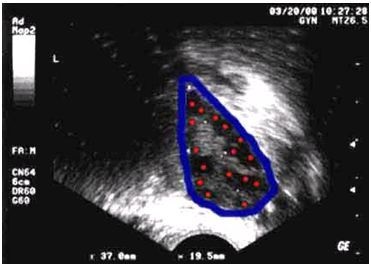

Így a gróf antrális tüszők látható ultrahang, helyettesíti a mikroszkópos vizsgálata a petefészket pontosan felmérni a tojások száma prekurzorok.

Antrális follikulus száma ultrahang - egy egyszerű és megfizethető módszer értékelésére petefészek tartalék.

Az 1. ábrán a bal oldali petefészek (bekarikázott kék), ahol a számlálási ablakban antrális tüszők korai a menstruációs ciklus (piros). Ez a nyúlvány 16 világos petefészek tüszők.